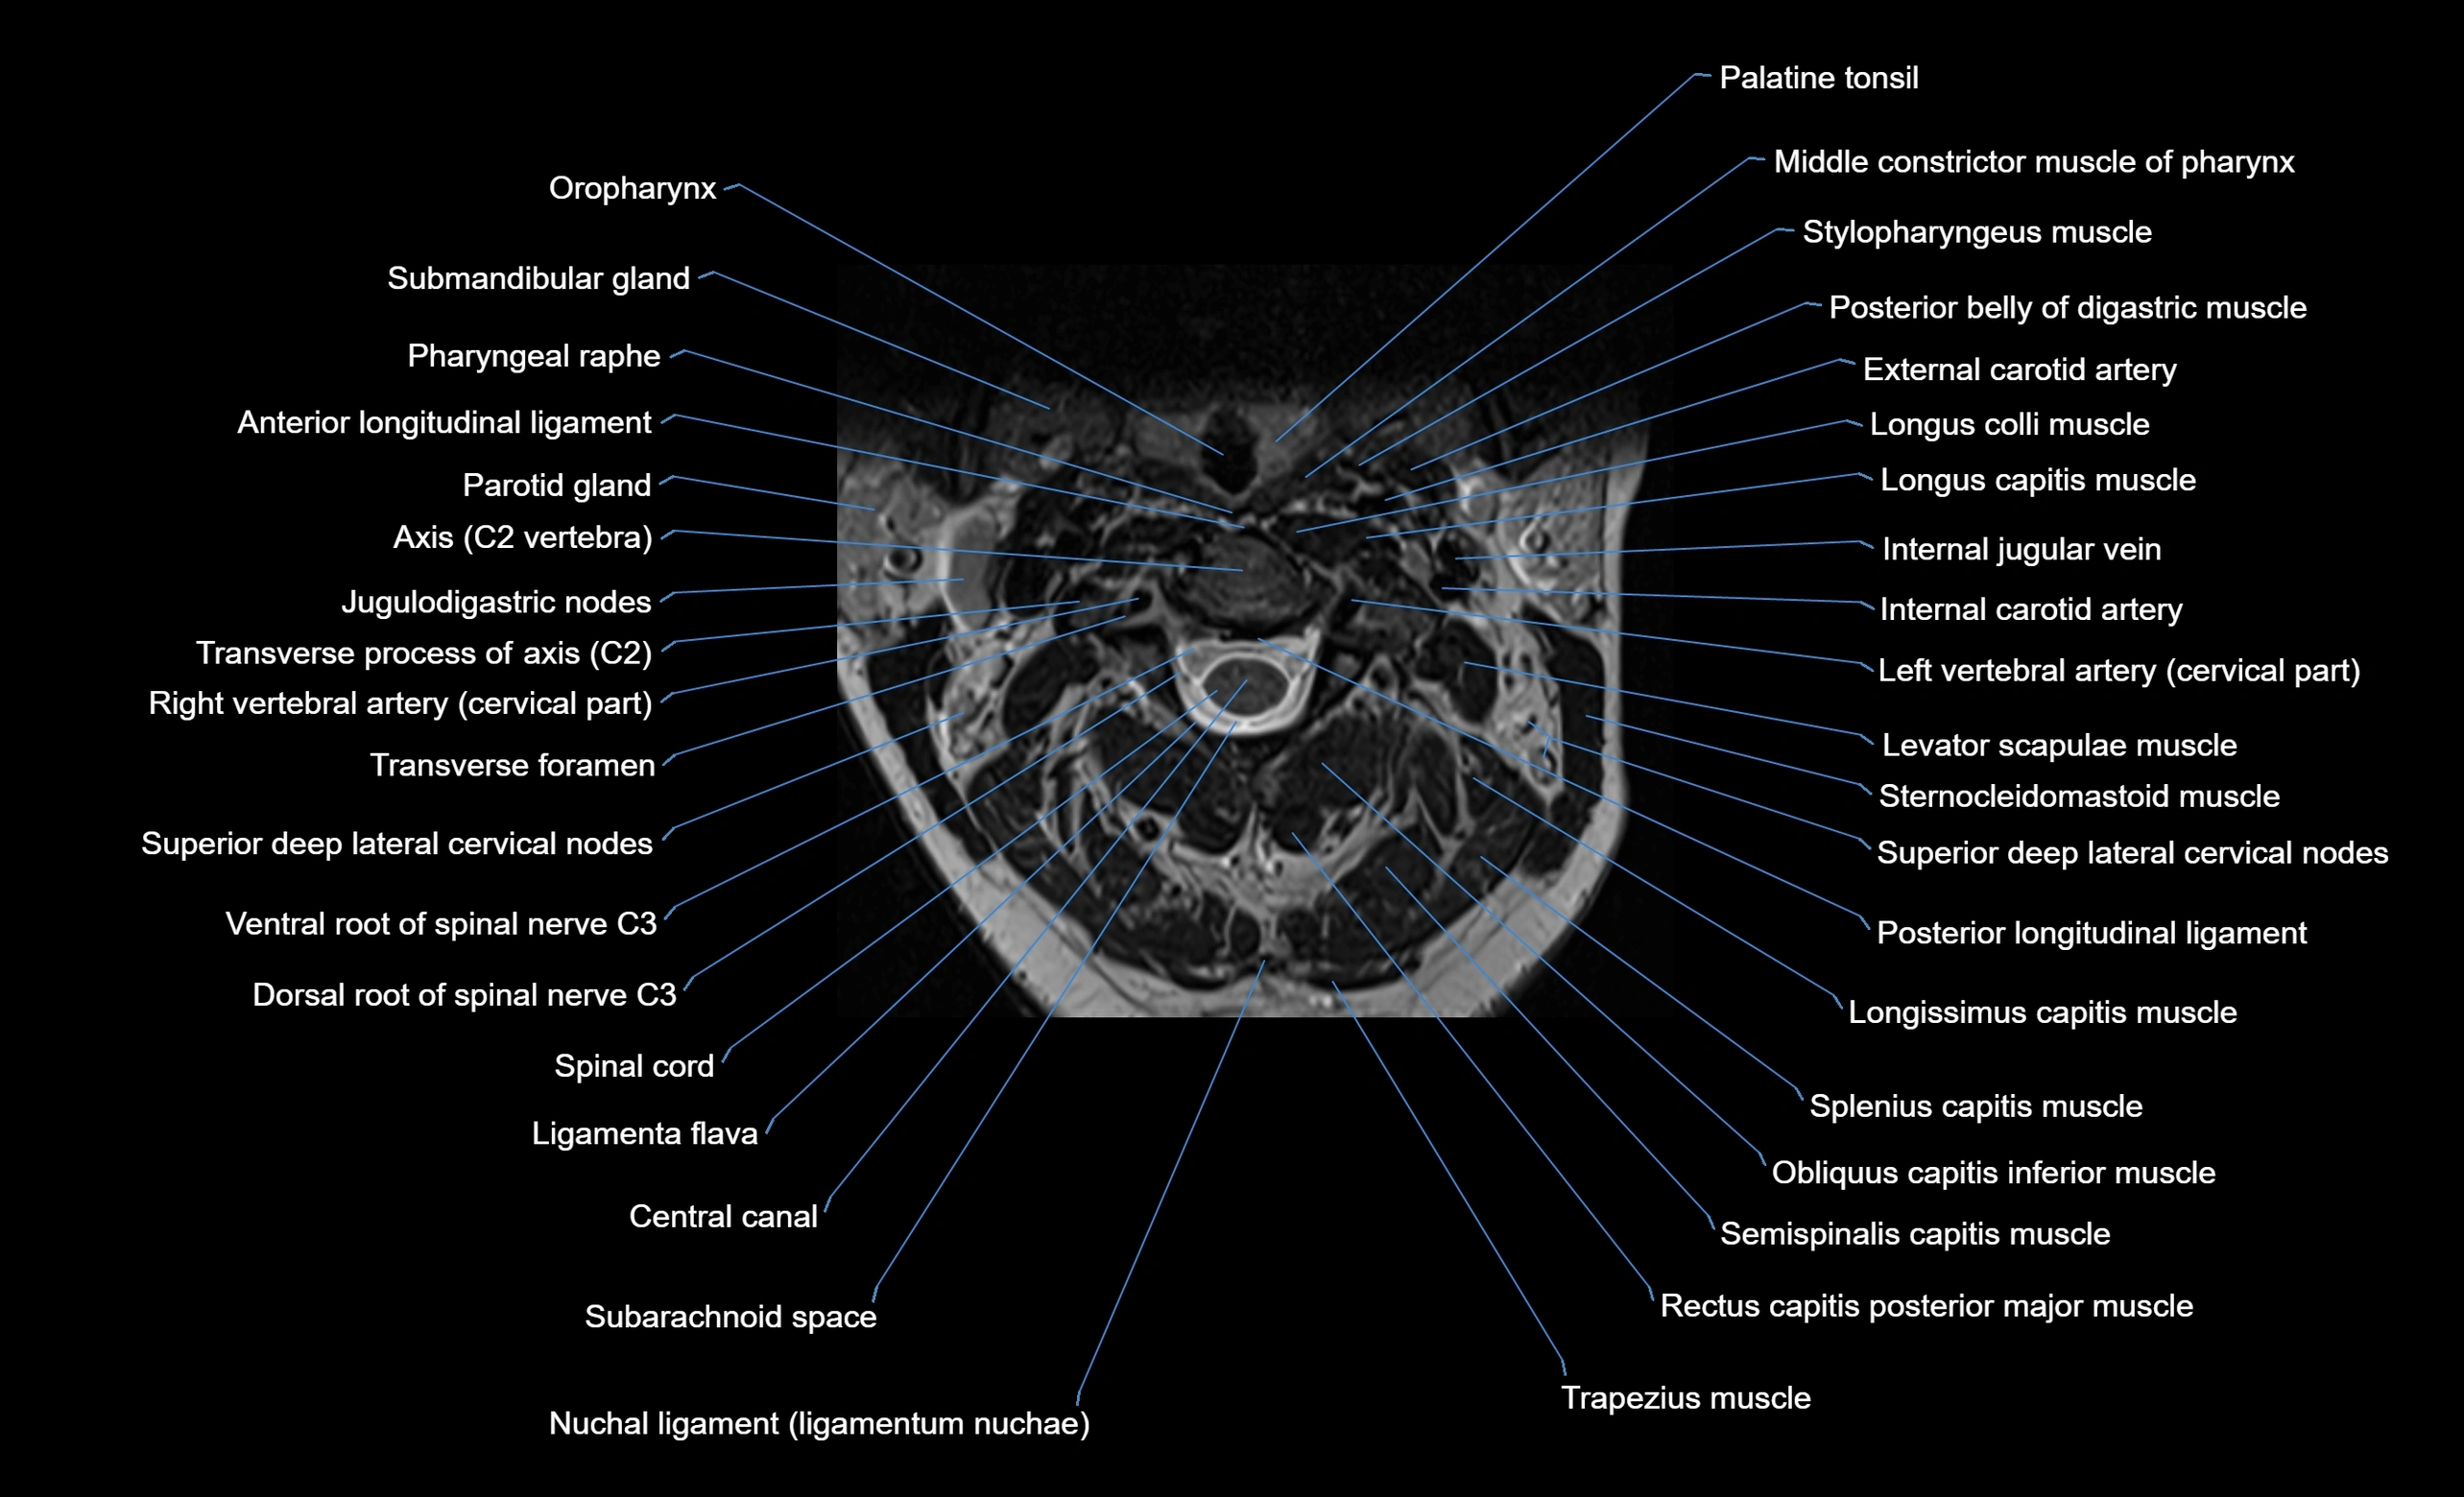

MRI appearance

T1-weighted images:

• Annular epiphysis: Low signal cortical rim at the vertebral margin

• Adjacent marrow: Intermediate-to-high signal in the vertebral body

• Disc interface: Clear delineation between bone and annulus

T2-weighted images:

• Annular epiphysis: Low signal intensity line

• Endplate cartilage (in younger patients): Intermediate signal

• Intervertebral disc: High signal nucleus pulposus

STIR:

• Annular epiphysis: Low signal cortical rim

• Adjacent marrow: Suppressed fat signal with preserved bony outline

• Utility: Highlights marrow and endplate interface in developing spine

MRI image

image